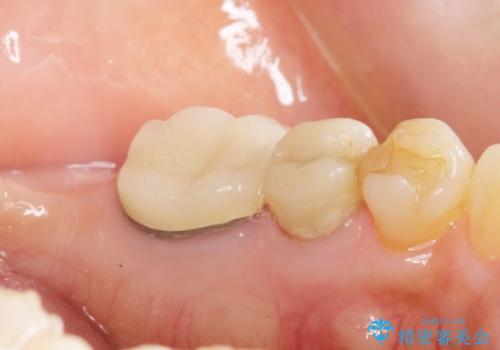

親知らずの移植 4年半経過症例 70代女性

- 親知らずの移植治療から4年半経過した患者様です。

移植した親知らずは全く問題ないそうで、「まるで自分の歯のようです。本当にすごい技術ですね。」とおっしゃって下さいました。

歯肉の腫脹や退縮、動揺も認められませんでした。